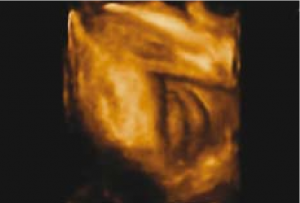

השתנה עוברית - Vijayaraghavn‏[30] דיווח על הדגמת השתנה עוברית גם בזכרים וגם בנקבות בשימוש באולטרסאונד רגיל וגם על ידי דופלר צבע. הדגמת מקור ההשתנה שימשה לאבחון שני עוברים עם היפוספאדיאס. שימוש Power Dopplerf עזר לנו לאבחן שלושה עוברים עם היפוספאדיאס, בשניים מהם הודגם מקור השתן מבסיס הפין ובשלישי מאמצע הפין. אולטרסאונד תלת מימדי - מנסיוננו, שימוש באולטרסאונד תלת מימדי אינו מוסיף משמעותית לאבחון מין העובר, במיוחד בטרימסטר הראשון ותחילת הטרימסטר השני ולעתים יכול אפילו להטעות (תמונה 6). Benoi‏[9] ואחרים[31], [32] הגיעו למסקנה שאכן התלת מימד אינו עוזר לאבחון מין העובר אך השימוש בחתכים (sectional planes) לעתים יכול לעזור על ידי הצגת החתך הסגיטלי האמצעי ביתר קלות ובכך לעזור לאבחון מין העובר. בטרימסטר השני והשלישי התלת מימד יכול לעזור בהצגת איברי המין להורים בצורה יותר משכנעת (תמונות 7 ו-8). בחלק מהמקרים עם מומים באיברי המין החיצוניים, התלת מימד יכול להדגים את המום ולעזור להגיע לאבחנה, כפי שנדון בהמשך.

תמונה 7. איברי מין חיצוניים של זכר בשבוע 34 בתלת מימד

400 פיקסליםתמונה 8. איברי מין חיצוניים של נקבה בשבוע 32 בתלת מימד